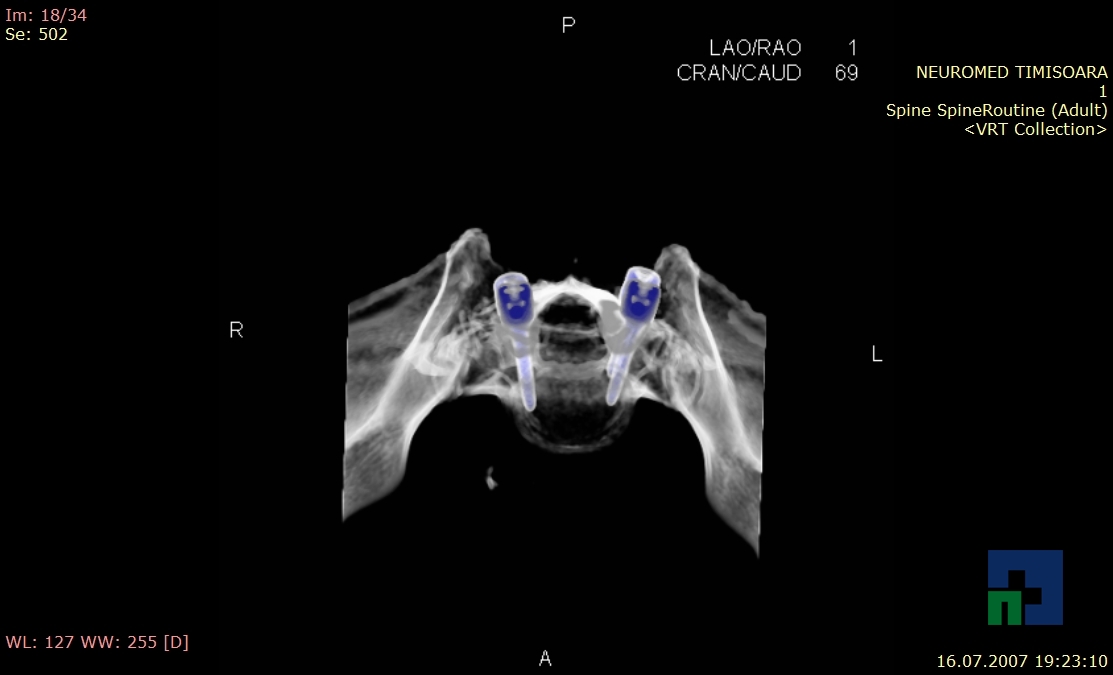

- Diagnosticul fracturilor:

- Unice

- Multiple

- Cu înfundare

- Complexe cranio-sinusale

- Complexe cranio-etmoidale

- Complexe cranio-orbitare

- Complexe cranio-faciale